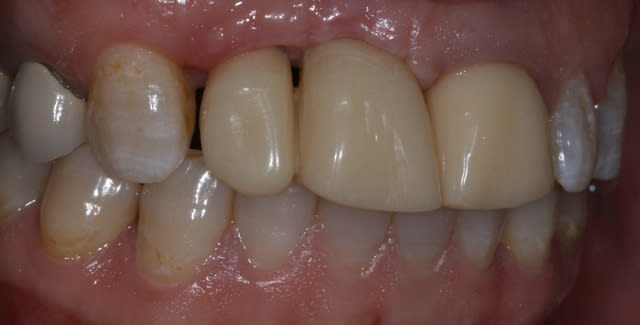

Patiente de 30 ans suite à parodontite a perdu 11-12 avec grosse perte osseuse.

J'ai suffisamment d'os pour prévoir la pose implantaire sans greffe mais esthétiquement je pense que cela va être moche car la ligne du sourire me semble bien haute.

si tu implantes comme ça, on est bien d'accord que ça va être moche.

que comptes tu faire de la 21? as tu une rétro?

il y a un truc qui me chiffonne, tu dis que cette patiente de 30 ans, a perdu ses deux ans suite a une parodontite?, mais alors vraiment très très localisée, car je ne vois aucun problème ailleurs

Bon ben j'ai implanté avant d'avoir refait la 21. Du coup j'ai mésialé la pose de 11 pour compenser la distalisation de 21.

Au final je n'ai pas fait de greffe osseuse... et j'ai réalisé une technique de rouleau sur 11-12 mais je reste un peu court à mon goût.

J'ai mis en place des transitoires sur 11-12-21 pour temporiser 3 mois pour voir la maturation des tissus mous.